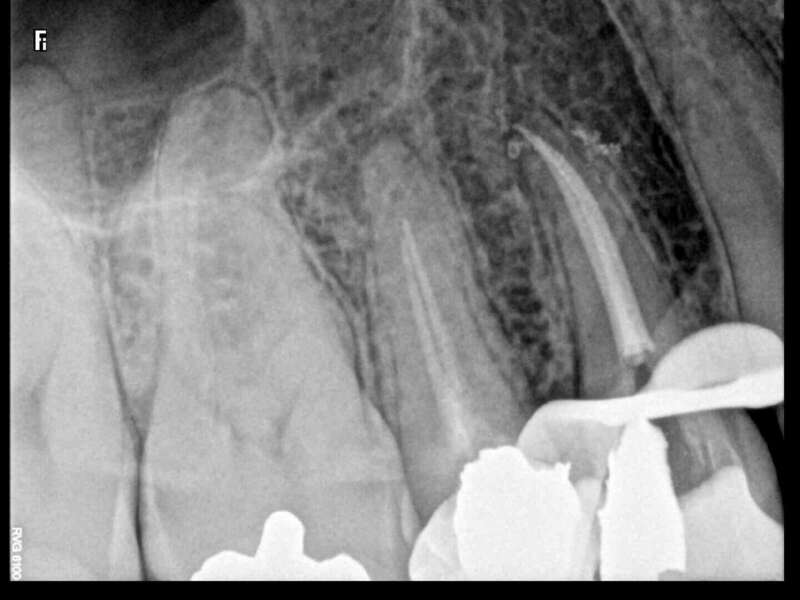

Cas du patient 3

Avant

Après